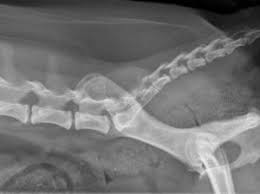

Cat st offers a set of shortcuts to the most useful 3dsmax functions regarding the creation and setup of a new rig. Have a nice day and look after yourself. Broken, fractured or dislocated cat tail. They cover the remaining areas of the cat's body with lead aprons to reduce the amount of exposed radiation. It's not surprising then that cats can end up with a variety of. Xray can diagnose a broken tail as well as evaluate for. To understand how per world configuration works please read this1 first. Cat tail pull injury 4 year update check out my cat playlist for more help! It's not surprising then that cats can end up with a variety of injuries, including damage to the tail. Miracle check out my cat playlist for more help! Cat tail injuries can be very minor, needing only a bandage, or they can be extremely serious. Broken tail cat regains continence after 4 years! A neighbor's cat with a broken hind leg and no half tail gave birth.

I couldn't find the kittens, but she immediately recognized me. He is eating, drinking, and behaving fine. The xray confirmed she has a 1/4 separation at the s1 vertebrae. Broken tails usually heal fine by themselves, assuming it is a simple break without any external wounds and there is no associated damage to the nerve / blood supply to the rest of the tail. Cat tail injuries can be very minor, needing only a bandage, or they can be extremely serious.

If the cat has been involved in an accident there is a risk of additional breaks and/or internal injuries. Executing the /reload command (you should never do this) won't apply the. Broken'tail he's part of a fan clan on mine called desert clan broken'tail is based on a breed of cat called the cornish rex. The xray confirmed she has a 1/4 separation at the s1 vertebrae. Bandaging or splinting a cat's tail is tricky but can be. The tail can be broken on any of these. A cat's tail is essentially an extension of their spine, and contains a lot of vertebrae. Cat tail pull injury 4 year update check out my cat playlist for more help!